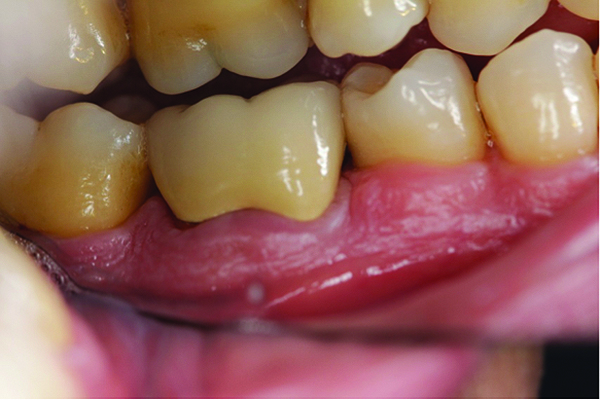

Fig 9. Case 2 clinical photograph showing the large size of the patient’s tonsils.

Figure 9

A 46-year-old Hispanic woman presented to the office stating the following: “I have terrible breath that smells like rotting eggs that is especially strong in the morning.” Her medical history was non-remarkable, and she reported having a professional dental cleaning 6 months prior. The patient was a non-smoker, non-drinker, and reported being very fond of onions. Evaluation of the oral cavity revealed no caries or periodontal inflammation, but the large size of the patient’s tonsils was noted (Figure 9).

The patient was instructed to keep a daily journal describing her perception of the oral malodor at the end of each of these 3 weeks. In addition, the patient was referred to an ENT specialist to evaluate her tonsils as the possible etiology. The patient was diagnosed as having deep tonsilar crypts in which food debris and bacteria were being lodged. Discussion between the dental team and the medical doctor concluded that if neither the chlorhexidine nor hydrogen peroxide rinses were effective in keeping the tonsilar area clean, surgical removal of the tonsils would be discussed with the patient as a treatment option.

During the patient’s re-evaluation appointment a month after her initial visit, the patient reported the following observations from her journal: the week of eliminating odorous foods from her diet did not resolve malodor; she noticed improvement with use of the chlorhexidine rinses but complained of the brown residual staining left on her teeth as a result; improvement was also noted with use of the hydrogen peroxide rinse. These were evidence that the tonsilar crypts were retaining food and bacteria and were the etiology of her halitosis.

After discussing the findings with the ENT doctor along with these outcomes, it was determined that the hydrogen peroxide rinse should be incorporated into her daily home hygiene regimen, and surgical intervention was not needed at this time. The patient was and continues to date to be satisfied with this result.